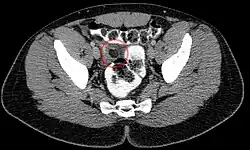

Appendicitis epiploica in der Computertomographie: Das umgebende Fett ist entzündlich verdichtet.

In seltenen Fällen kann es zu einer Verdrehung (Torsion) und zu einer Infarzierung dieser Anhängsel kommen, die dann schmerzhaft ist und je nach Lage der betroffenen Appendix mit einer normalen Appendizitis oder auch mit einer Sigmadivertikulitis verwechselt werden kann.[2] Man spricht dann von einer Appendicitis epiploica. Im englischen Sprachraum wird auch von einer Epiploic appendagitis[3] gesprochen, um eine Verwechslung mit der Appendizitis des Wurmfortsatzes zu vermeiden.